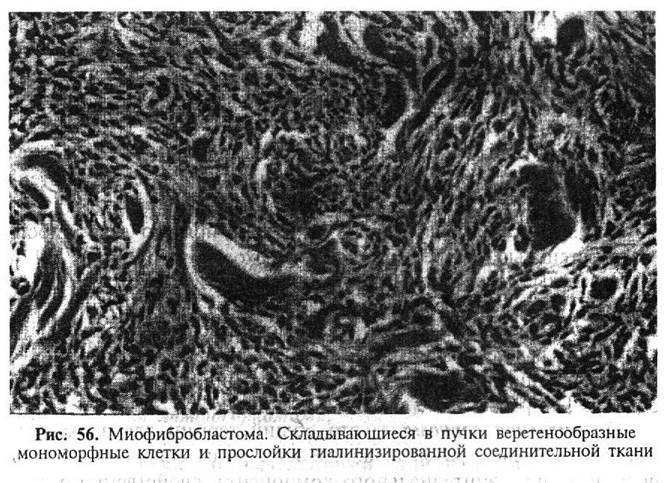

Миофибробластома (рис. 56) - доброкачественная опухоль, имеющая вид четко очерченного плотного узла, на разрезе равномерного белого цвета. Микроскопически состоит из веретенообразных мономорфных клеток, складывающихся в пучки, которые обычно разделены широкими тяжами гиалинизированного коллагена. Иногда выявляются очаги хрящевой и костной метаплазии.